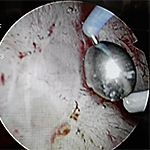

Q.内視鏡的治療はどのようなものがありますか?

- 膀胱水圧拡張術は保険で認可された唯一の治療法です。

- ハンナ病変を認める場合、電気やレーザーによる焼灼術が行なわれ、疼痛に対しては有用な治療法と考えられています。

- ハンナ病変に対する電気焼灼術は、疼痛に対しては有用な治療法と考えられています。

(術後速やかに疼痛は減少し、治療効果は12ヶ月以上持続)

M. Kajiwara, et al. IJU 21 (Suppl 1), 57–60. 2015.